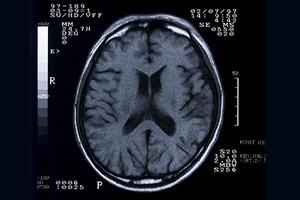

- 【2026年最新版】安心と信頼の「近くの脳神経外科」徹底ガイド:最適な医療機関の選び方と最新情報

- 脳に関する症状や不安を抱えている場合、最も重要なのは適切な専門医に相談し、正確な診断と適切な治療を受けることです。特に、頭痛やめまいを頻繁に感じたり、記憶力の低下や意識の乱れ...